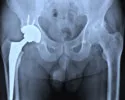

Limburgse ziekenhuizen plaatsten omstreden kunstheup

Sittard-Geleen, 25-05-2012 | Mensen met een metaal-op-metaalkunstheup moeten een klacht indienen bij het ziekenhuis waar die heup geplaatst is. Dat vindt patiëntenorganisatie NPCF... bron: www.l1.nl